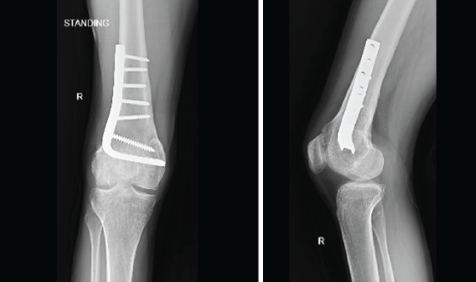

Post-operative radiograph (Fig. 7) was taken and showed good correction of mPDFA. He was started on non-weight-bearing mobilization with a long knee extension brace and walker support from post-operative day 1. Active knee mobilization exercises were also started, and his wound healed uneventfully.

Figure 7: Post operative radiograph

He was routinely reviewed and was started on full weight-bearing mobilization at 2 months post-operative. He was reviewed recently at 2 years post-operative period and showed excellent functional outcome with full pain free active range of movements of right knee from 0° to 150° (Fig. 8). He was able to do straight leg raise (Fig. 8) independently and had full extension- 0° (Fig. 8). No limb length discrepancies were noted (Fig. 8) and bilateral stance from anterior (Fig. 8) and posterior aspects (Fig. 8) were also normal. Post-operative radiograph showing the knee with distal femur AP (Fig. 9) and lateral views (Fig. 9) showed union of the osteotomy with no signs of implant failure or loosening and good correction of the mPDFA.

Figure 9: Post operative follow up radiography